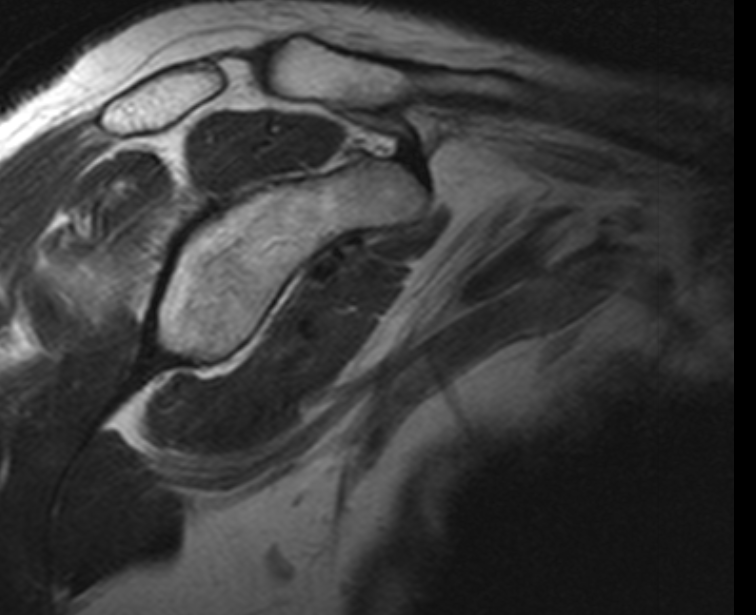

The normal shoulder has several layers.These layers mean that the shoulder joint is several centimeters below the skin. Swelling in the shoulder is not easily seen unless it is very severe.

Deep to the deltoid run muscles from the shoulder blade attaching to the top of the humerus just at the edge of the joint. These muscles are known as the rotator cuff. They form a near continuous attachment to the bone so an injury to the tendon (the white sinewy part of the muscle that attaches to the bone) of one muscle often extends into its neighbouring rotator cuff muscle.

Deep to the rotator cuff lies the deepest layer of soft tissue, the joint capsule. The capsule is a thin but strong fibrous layer that is supple enough to allow full movement but strong enough to stop the shoulder dislocating. It is inflammation in the joint capsule which causes the capsule to stiffen reducing movement causing the symptoms of a frozen shoulder. At the opposite extreme tearing of the capsular attachment to bone is what allows shoulders to dislocate.

Beneath all these layers lie the cartilage covered bones of the shoulder joint formed by the humeral head (top of the humerus) and the glenoid (the oval joint surface of the scapula). Arthritis in the bones of the shoulder joint results in loss of the white shiny and smooth articular cartilage leaving the much rougher bones directly in contact with each other.